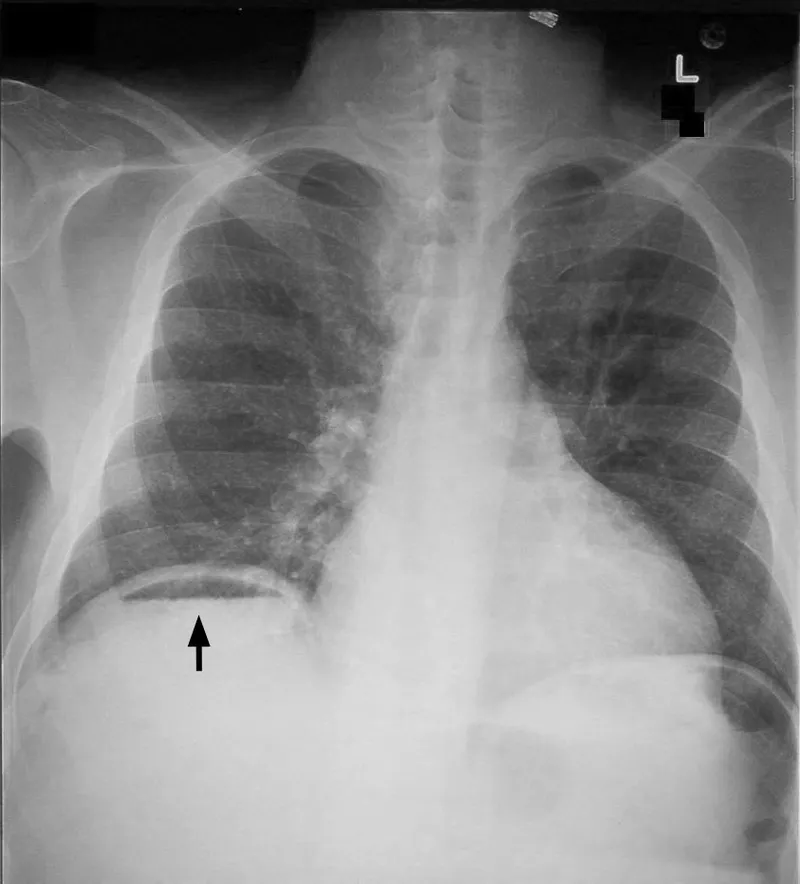

- Erect AP: Detects free intraperitoneal air (under diaphragms), air-fluid levels.

- Pneumoperitoneum: Free air (perforation).

- Key Signs:

- Rigler's sign 📌 (bowel wall visible)

- Cupola sign (subphrenic air)

- Football sign (massive)

- Best View: Erect CXR, L. Lat. Decubitus.